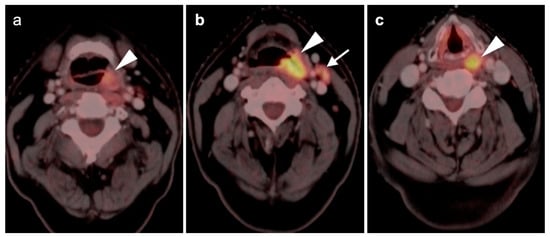

2.3. Nasopharyngeal Carcinoma

2.5. Major and Minor Salivary Gland, Lacrimal Gland Tumors

- Warthin tumor